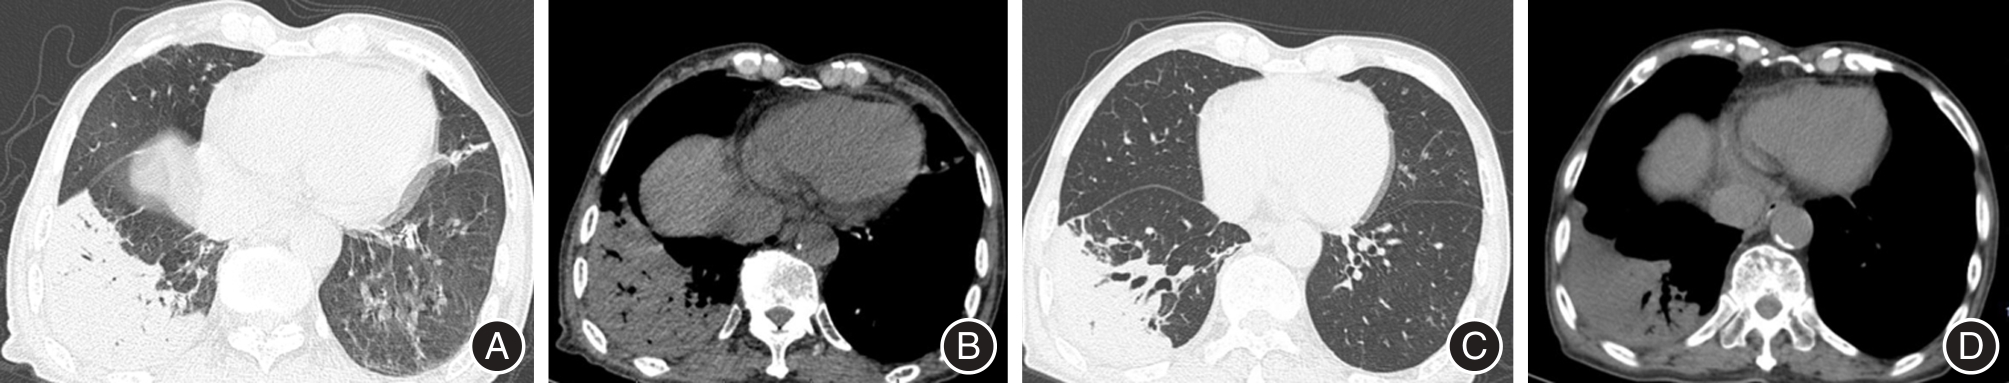

SHA L, LI W, NA C, et al. Differential clinical and CT imaging features of pneumonic-type primary pulmonary lymphoma and pneumonia: A retrospective multicentre observational study[J]. BMJ open, 2023, 13(10): e077198-e077198. doi: 10.1136/BMJOPEN-2023-077198 .